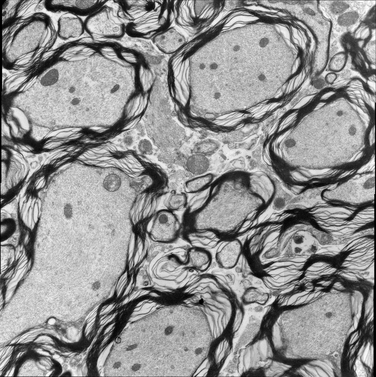

For image analogies based image registration, I have corresponding TEM/Confocal Microscopic image pairs of mouse brains with corresponding regions highlighted by a box. Using the correlative microscopy technique on the mouse brain, I want to localize specific brain regions associated with Pelizaeus-Merzbacher Disease (PMD) and do quantitative assessment of hypomyelination and demyelination in mice. PMD is one of a group of genetic disorders characterized by progressive degeneration of the white matter of the brain affecting the myelin sheath, the fatty covering that acts as an insulator on nerve fibers in the central nervous system.

The confocal microscopy images are multichannel color images in our test dataset. The blue channel is based on the blue stain DAPI (a fluorescent stain) which stains the DNA of the cell nucleus and corresponds to dark regions within the nuclei in the TEM. The green channel is based on the stains of the myelin sheats, visible as dark black layers covering the neurons in the TEM images. The red channel is not explicitly stained for and is caused by the auto-fluorescent effect of lipofuscin. The confocal image with RGB channels and its corresponding TEM image are shown in Fig. 5.

(f) TEM image

Figure 5: Example of Confocal image with RGB channels and TEM image